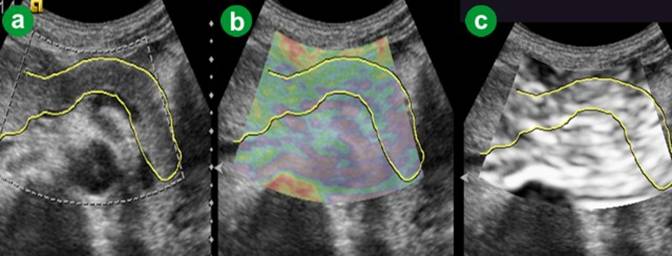

The ARFI-VTQ values for the pancreatic parenchyma ranged from 0.80 m/s to 2.21 m/s with a mean value of 1.276±0.293 m/s (Table 2, Figure 1). On eSie touch elastogram, normal pancreatic parenchyma and peripheral fat appeared white to light gray (scores 1-2) on gray scale while on the color scale, it was green/purple to yellowish green (scores 1-2), thus indicating softness of the normal tissue (Figure 2).

Figure 2. Normal pancreas. a. US B-mode image. b. eSie touch color scale image (green/purple to yellowish green: score 1-2). c. eSie touch gray scale image (white to light gray: score 1-2). |